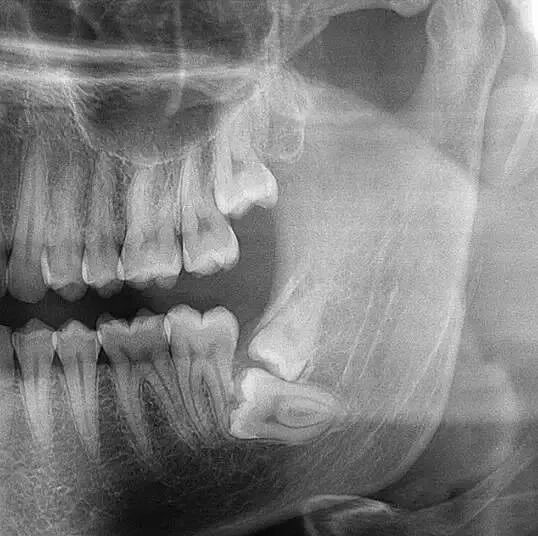

埋伏阻生牙 智齿俗称劲头牙,一般长在牙槽骨里,有的正常萌出,有的埋伏在牙槽骨里部分萌出或完全没有萌出。所以,拔除智齿需要拍全景片,医生才能看清楚牙齿长势、牙根位置以及和面部神经的距离! -

口腔全景片是口腔科检查中十分重要的常规检查手段,主要用于检查、分析、判断病情,帮助医生及时、正确的诊断,进而引导治疗工作。